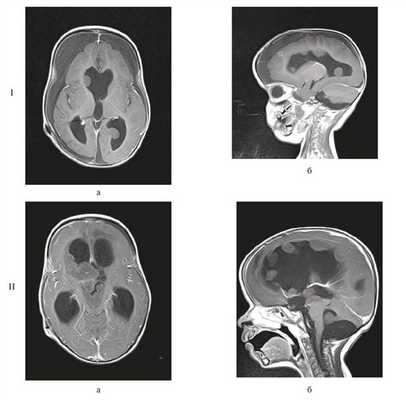

Девочка в возрасте 11 мес. Заболела остро, после перенесенной легкой черепно-мозговой травмы — упала с высоты собственного роста, после чего стала утрачивать приобретенные навыки: перестала стоять, сидеть, появилась вялость, адинамия, срыгивания. При МРТ головного мозга выявлена гигантская опухоль боковых и III желудочков, окклюзионная гидроцефалия (рис. 1).

Рисунок 1. Магнитно-резонансные томограммы грудного ребенка 11 мес с гигантской внутрижелудочковой опухолью. а — Т1 с контрастным усилением, аксиальный срез, б — Т1 с контрастным усилением, фронтальный срез.

Через 3 нед была проведена полихимиотерапия (ПХТ) по Протоколу Baby-POG, всего проведено 3 цикла. При контрольной МРТ головного мозга выявлено множество узлов опухоли, распространяющихся по желудочковой системе в зоне операции (рис. 7).

Рисунок 7. МРТ головного мозга. I — после 1-го курса ПХТ (через 2 мес после радикального удаления опухоли); множество опухолевых узлов, распространяющихся по желудочковой системе; II — после 2-го курса ПХТ (через 9 мес после радикального удаления опухоли); метастазирование процесса (в виде многочисленных опухолевых узлов, распространяющихся по всей желудочковой системе). Режим Т1 с контрастным усилением: а— аксиальный срез; б — сагиттальный срез.